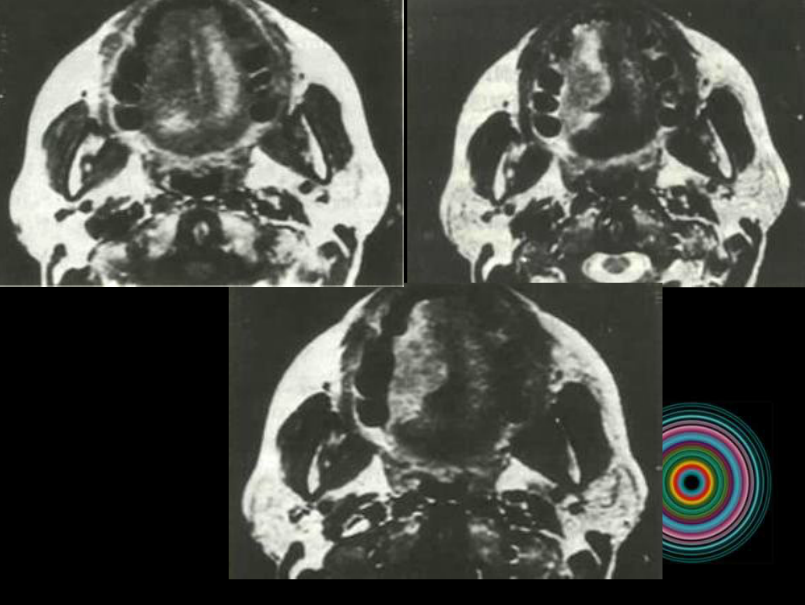

口腔頜面外科 影像技術(shù)